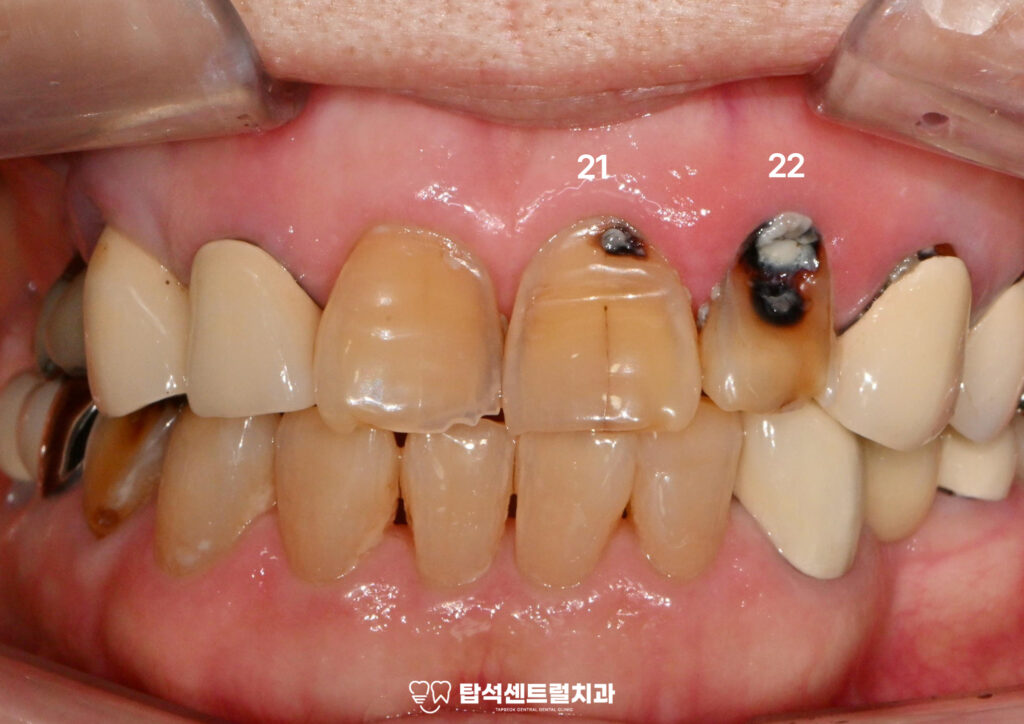

- 상악 좌측 전치부 치근 우식

의정부 치과 에서 준비한 구강 내 사진을 살펴보면

상악 좌측 전치부인 21, 22번 치경부를 중심으로

치근면까지 깊은 우식이 관찰됩니다.

해당 부위는 우식이 발생할 경우 진행 속도가 빠르고

광범위하게 퍼지는 경향을 보입니다.

특히 이번 증례에서는 치은연을 따라

우식이 치근 방향으로 진행되며

와동의 깊이 또한 상당한 상태였습니다.

치경부는 음식물 저류와 칫솔질이 어려운 부위이므로

플라그가 오랜 기간 정체되기 쉬운 환경이며,

치은 퇴축이 동반될 경우

이와 같은 치근 우식 발생 위험은 더욱 높아지게 됩니다.

또한 해당 부위는 타액 및 치은열구액의 영향으로

항상 습윤 상태가 유지되기 때문에

수복 시 격리가 어렵고 접착 안정성이

저하될 수 있다는 점 역시 임상적으로

중요한 고려 요소입니다.

따라서 본 증례와 같이 치근면까지

깊게 진행된 치근 우식의 경우에는

엑스레이를 통해 정확한 치료 계획을 수립해야 됩니다.